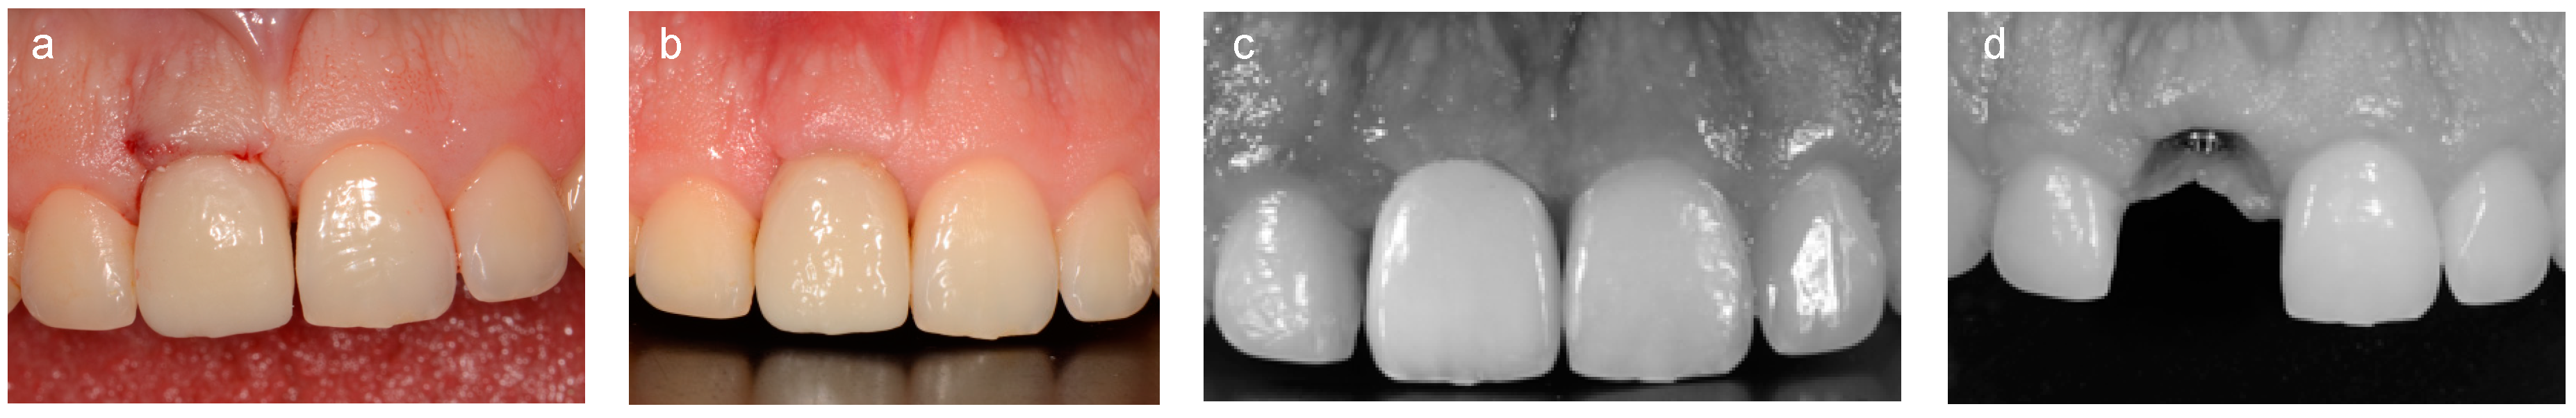

2.2. Analogic Work-Flow

2.3. Digital Work-Flow